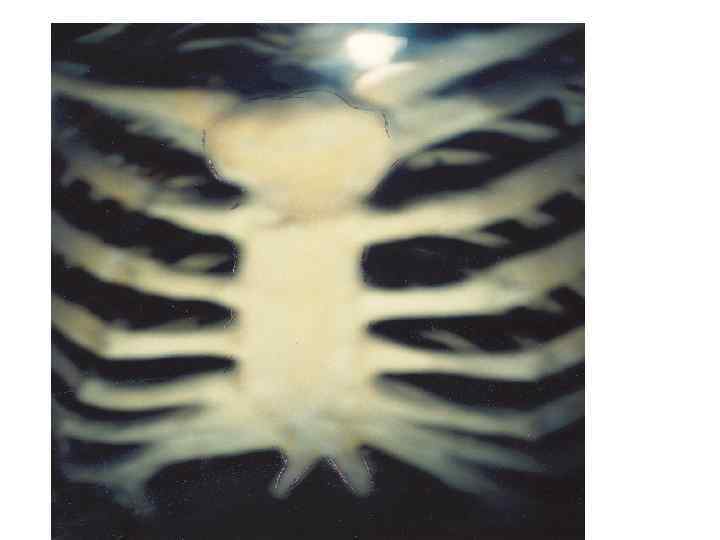

218. Гиалинді шеміршектіњ орнына с‰йектіњ дамуы (саусаќ c‰йектерiнiњ бойлыќ кесіндісі). Бояуы: гематоксилин - эозин. х 56. 1 - эпифизарлы гиалинді шеміршек; 2 - перихондрий; 3 - шеміршек баѓанасыныњ ќабаты; 4 кµпіршікті шеміршек ќабаты; 5 перихондральды с‰йек манжеткасы (перихондральды с‰йек); 6 эндохондральды с‰йек; 7 - периост - с‰йекќап (И. В. Алмазов, Л. С. Сутулов бойынша).